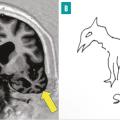

Il pourrait apparaître désuet de s’intéresser à l’anatomie macroscopique de la mémoire. Les mécanismes intimes de cette fonction cérébrale complexe mettent en effet en jeu des circuits neuronaux et des phénomènes de neurogenèse qui relèvent de mécanismes survenant à l’échelle microscopique.Néanmoins, certaines structures anatomiques…

1 - Les phénomènes mnésiques mettent en jeu à l’échelle microscopique des circuits neuronaux et des processus de neurogenèse. Néanmoins, certaines structures anatomiques clés comme l’hippocampe ou le lobe limbique ont un rôle central. L’hippocampe intervient dans l’acquisition, le stockage et la distribution des informations…